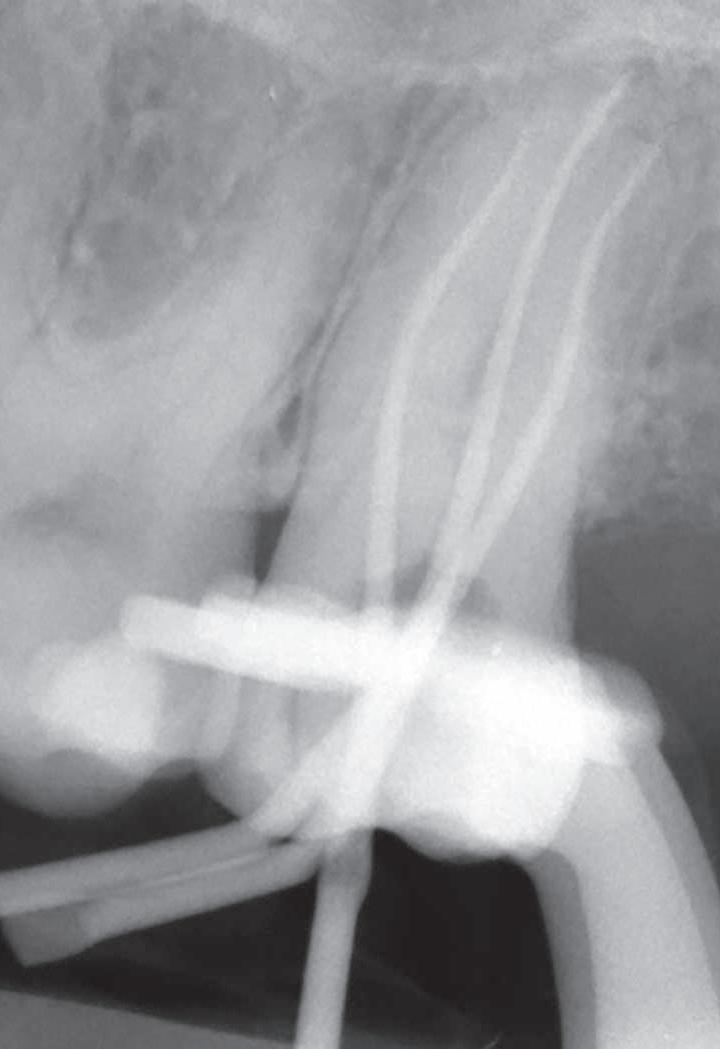

Abb. 1: Präoperatives Röntgenbild Zahn 27.

Der Fall: Irreversible Pulpitis Regio 27 Im Februar 2024 stellte sich eine 46-jährige Dame mit starken Schmerzen im linken Oberkiefer in unserer Praxis vor. Nach positiver Vitalitätsprobe, aber umso stärkerer Reaktion auf den Perkussionstest wurde in der Röntgendiagnostik eine irreversible Pulpitis an Zahn 27 bestätigt (Abb. 1). Die Patientin stimmte einer zweizeitigen Wurzelkanalbehandlung zu, welche direkt in derselben Sitzung angegangen wurde.